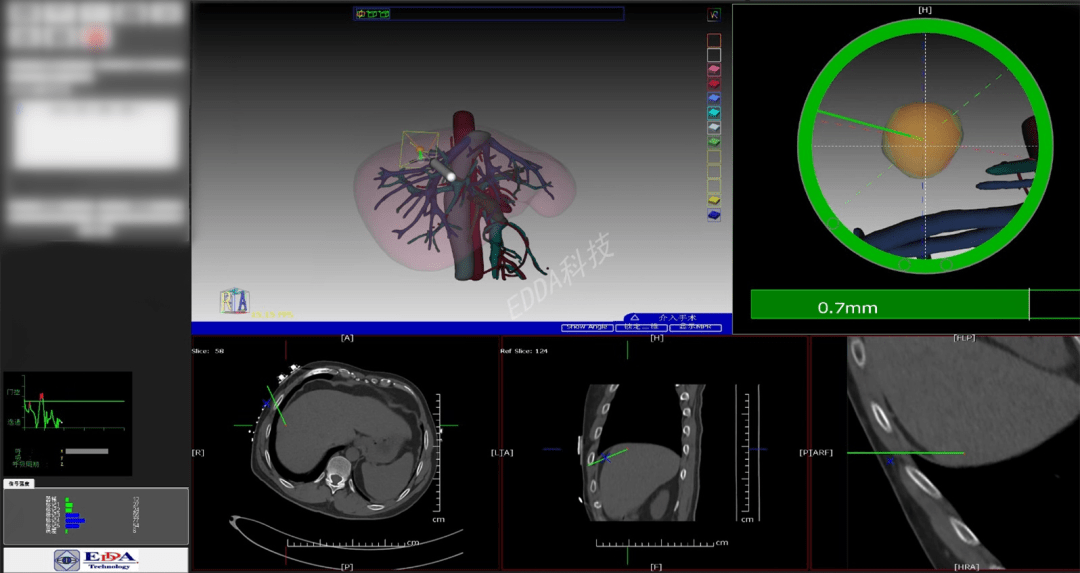

高新院区肿瘤科负责人余锋教授、副主任医师石超联合影像科主任王敏君等通过IQQA平台一同合作完成了患者术前“IQQA 个体3D全量化脏器电子地图”的构建和治疗模型。通过实时模型,石超医师详细为患者讲解了手术计划、麻醉评估、实施流程和风险控制。

CT进行3D重建,进上图:IQQA术前eO时制导路径,将消融治疗针精确送入目标病灶位置,成功实施肝脏转移灶的全范围微波消融。手术顺利,患者无明显不适,术后复查CT,微波消融范围理想,无术后并发症。

上图:IQQA术前eOrganMap三维重建及手术规划